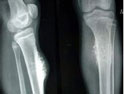

軟骨肉瘤是常見的惡性骨腫瘤之一,發(fā)生于髓腔者為中心型,發(fā)生于骨膜者為骨膜型,另有少數(shù)可發(fā)生于軟組織。腫瘤好發(fā)于四肢長骨與骨盆,也可見于椎骨、骶骨、鎖骨、肩胛骨和足骨。本病分原發(fā)和繼發(fā)兩種,后者可由軟骨瘤、骨軟骨瘤惡變而來,這也是發(fā)病年齡較晚的原因之一。本病多見于成人,30歲以下少見,35歲以后發(fā)病率逐漸增高。男性多于女性。